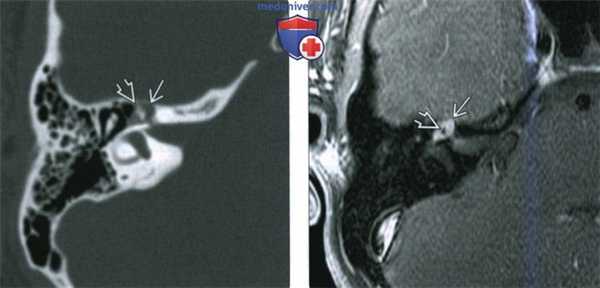

(Слева) При аксиальной КТ в костном окне у пациента с полипом в наружном слуховом канале определяется опухоль неправильной формы, расположенная в области сосцевидного сегмента ЧН VII.

(Справа) При аксиальной MPT Т1 ВИ С+ FS у этого же пациента определяется контрастирующаяся ШЛН в сосцевидном сегменте ЧН VII, выбухающая через костный дефект в НСК.